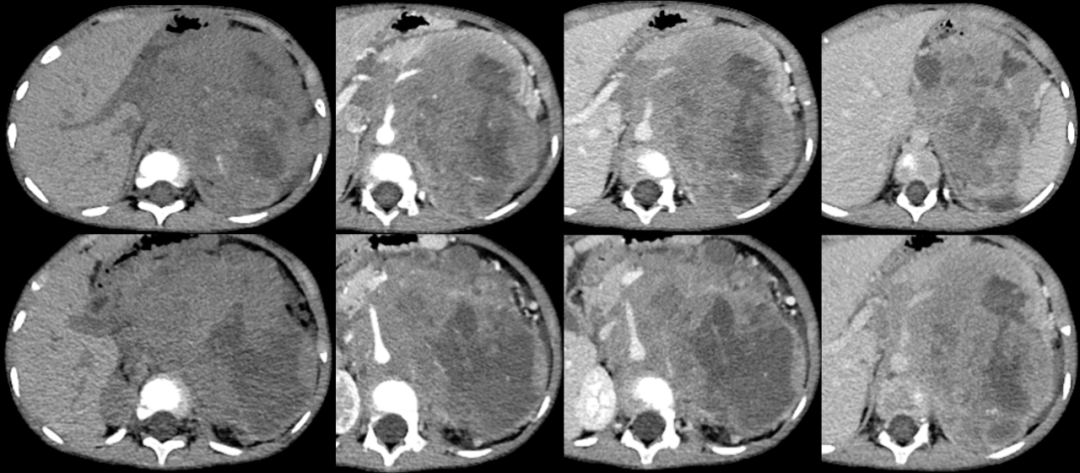

病例一

男,7 岁,因「发现左腹部包块 1 个月入院」。

影像描述:胰体尾部后方左肾前内方见团块样软组织密度影,大小约 7.6 cm×5.8 cm,CT 值约 36 HU,略呈轻度强化,其内见多发结节样钙化影,病变与左侧肾上腺分界不清,包绕左肾动静脉,未见变窄,其内另见左肾静脉分支迂曲走行。